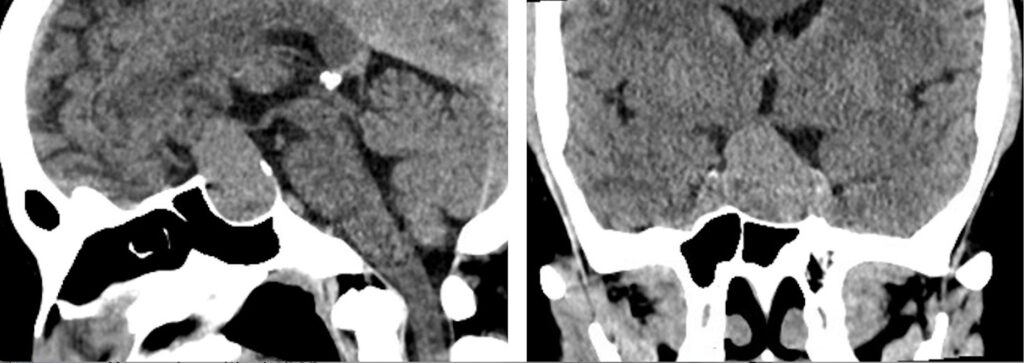

37歳女性 下垂体線腫を内視鏡手術しました。両耳側の視野欠損が回復しました。

若いですが、視野狭窄で発見された下垂体線腫を内視鏡で摘出しました。トルコ鞍前壁を十分に削除することで、上方の腫瘍残存をなくし、術後出血を防止できました。一過性に尿崩症が出現しましたが、コントロールされ退院されました。